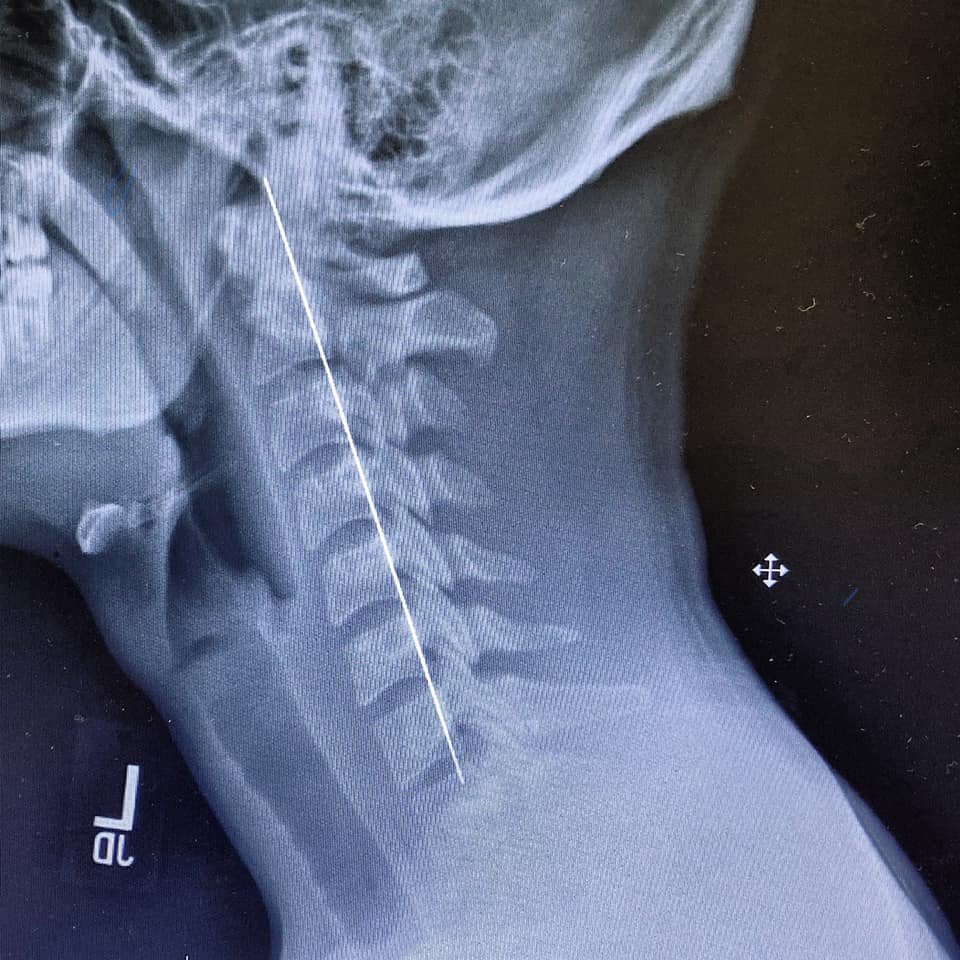

Some of the most common problems in today’s lifestyle are related to muscles and bones. Neck pain, back pain, lower back pain, disc problems are some of the many issues that we can face in our lives. If you are looking for a good neck pain treatment in Culver City, you can easily count on Dr. Mina.